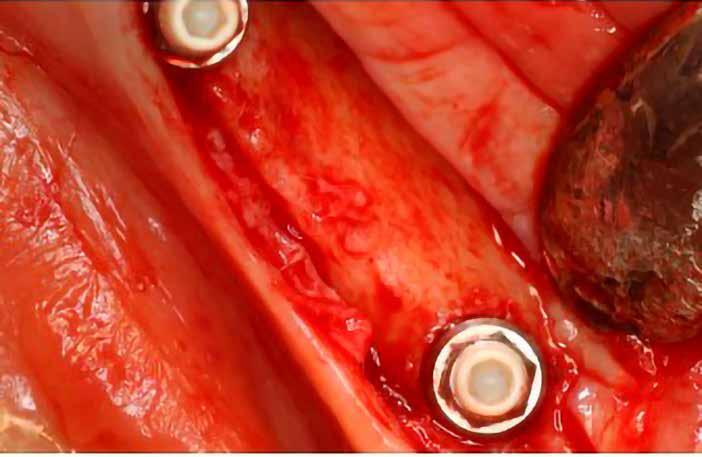

1. ábra: A műtét előtti szituáció, megfigyelhető az implantátumok közötti konkáv terület, ahova könnyen beragad az ételmaradék, és könnyen kialakul a periimplantitis.

Egy 47 éves páciens jelentkezett nálunk egy alsó, hátsó foghiánnyal, ahol jelentős csontfelszívódást tapasztaltunk a moláris fogak korábbi eltávolítása miatt (1. ábra). Két implantátum körül is volt ínyrecesszió, illetve a keratinizált íny mennyisége minimális volt (kevesebb, mint 1 mm). 4 hónappal az implantációt követően ínykorrekciót végeztünk.

Helyi érzéstelenítést végeztünk a műtéti területen artikain és 1:100 000 adrenalin segítségével. A recipiens területet előkészítettük, élesen disszekciót végeztünk, hogy egy izomtapadástól mentes periosteum ágyat képezhessünk. Ettől disztálisan két párhuzamos parakresztális metszést végeztünk egy 15C-s szikepengével, majd a metszéseket egy

2–5. ábra: A metszések és a deepitelizáció. – 6–9. ábra: Félvastag lebeny. – 10. ábra: A nyelezett ínylebeny „bepróbálása”.

horizontális metszéssel kötöttük össze (2–5. ábra). A metszések hosszát és a köztük lévő távolságot minden esetben a lágyszövet augmentációhoz szükséges keratinizált szövet határozza meg. A lebeny deepitelizációját egy 15C-s szikepengével végeztük (6. ábra). Ezt követően félvastag lebenyt preparáltunk (7. ábra). A lebenyt apikálisan, az alapjáról belső, felületes metszéssel felszabadítottuk, hogy passzívan áthelyezhessük és rögzíthessük, feszülés nélkül. Meziális irányba 180 fokkal átforgattuk (8–9. ábra). A meziális papillát alagúttechnikával (tunnelling technique) készítettük elő a graft befogadására (10. ábra). Az így kialakított lebenyt a recipiens ágyban rögzítettük az újonnan kialakított vesztibulum alapjánál 5-0 nem felszívódó PTFE (Coreflon, IMPLACORE) varratokkal. A graftot behajtottuk az ínyszél alá és meziális oldalon rögzítettük PTFE varratokkal (11–14. ábra) A műtétet követően napi kétszeri, 0,12%-os klórhexidin tartalmú szájvízzel történő öblögetést javasoltunk a páciensnek, két héten keresztül. Gyulladáscsökkentésre 8 óránként 400 mg Ibuprofént javasoltunk, három napon keresztül. A páciens elmondása szerint sem fájdalmat, sem különösebb diszkomfortot nem tapasztalt. Ezt követően, további 4 héten keresztül, 0,2%-os klórhexidin tartalmú szájvízzel történő öblögetést javasoltunk a betegnek és instruáltuk, hogy lehetőleg ne mossa fogkefével az érintett területet. A varratokat egy héttel később távolítottuk el. A donor és a recipiens terület – 10 nappal a műtétet követően – kiválóan gyógyult (15–16. ábra). Az ezt követő kontrollokat a következő időpontokban ejtettük meg: kettő, illetve négy héttel a műtét után, majd három, hat és tizenkét hónappal később, ezt követően pedig félévente (17–20. ábra). Minden kontroll alkalmával professzionális fenntartó kezelést végeztünk a területen.